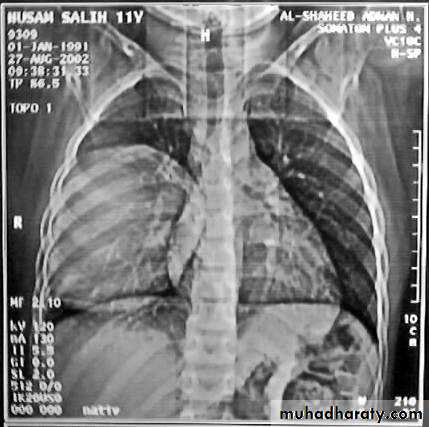

• 7-Diaphragmatic injuries Trauma can lead to rupture of the diaphragm ,most commonly the left side affected ,leading to herniation of the viscera .Stomach is the most frequent organ to herniated followed by the transverse colon , spleen leading to collapse of the lung and mediastinal shift which can be seen on chest X-ray .Barium study is of great help in the diagnosis .Treatment surgery through abdominal , thoracic ,combined approach or by laparoscopy .